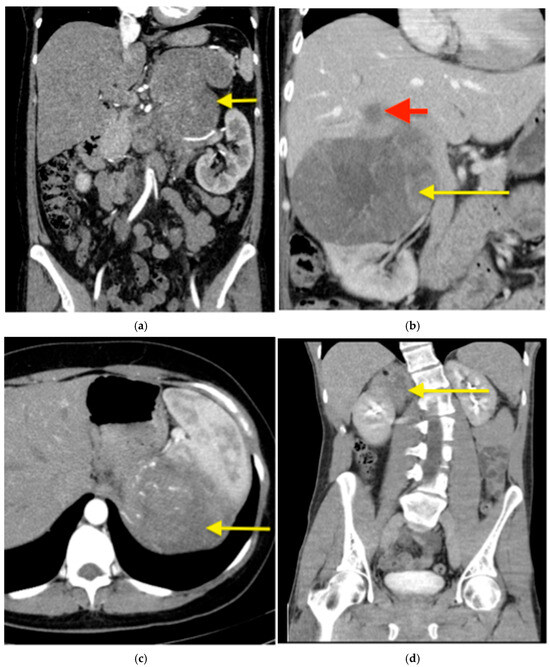

The intra- and postoperative outcomes are shown in Table 2. Open surgery was performed in 18 patients (85.7%) and a hybrid approach in 3 patients (14.3%). The median duration of surgery was 236 min [range 102–825 min]. R0 resection was achieved in 16 patients (76.2%). Blood transfusion was required in 6 cases (28.6%). Most patients (20 of 21; 95.2%) required an ICU stay, with a median duration of 1 day [range 1–38]. The median length of postoperative hospital stay was 12 days [range 6–78]. Postoperative complications occurred in 9 patients (42.9%), including 6 minor (28.6%) and 3 major complications (14.3%). The most commonly resected organs were the kidney (n = 11; 52.4%) and the liver (n = 6; 28.6%). Indications for multivisceral resection included adhesions to adjacent organs (n = 4; 19.1%), suspected infiltration of surrounding organs or vessels (n = 7; 33.3%), liver metastases (n = 4; 19.1%), the need for improved surgical exposure (n = 1; 4.8%), and the presence of tumor thrombus (n = 1; 4.8%). Of the four patients (19.1%) who underwent multivisceral resection due to suspected organ infiltration, liver involvement was histologically confirmed in two (9.5%) and diaphragmatic infiltration in one (4.8%). No pathological evidence of infiltration was found in the resected kidneys, pancreas, or spleen. In 18 patients (85.7%), the suspected diagnosis of ACC was confirmed histologically. The remaining three patients (14.3%) were diagnosed with other tumor entities: one sarcoma, one adrenal metastasis of non-small cell lung carcinoma, and one ganglioneuroma. Examples of preoperative CT scans of patients with suspected ACC and organ infiltration are presented in Figure 1.

Figure 1. Suspected ACC in computed tomography (CT)—examples. (a) A CT with contrast of a 42-year-old female patient with a left sided ACC (arrow) producing cortisol, testosterone and dehydroepiandrosterone, measuring 170 mm in the largest diameter with a suspected infiltration of renal hilum. The adrenal tumour was resected en bloc with the left kidney. (b) A CT with contrast of a 49-year-old female patient with a right-sided, cortisol producing ACC (yellow arrow), measuring 150 mm in largest diameter with a liver metastasis in segment VII (red arrow), which was resected en bloc with the adrenal tumour. (c) A CT with contrast of a 39-year-old female patient with a hormonally inactive left-sided ACC (arrow), measuring 215 mm in the largest diameter. Preoperatively suspected adhesions to the spleen in the preoperative cross-sectional imaging were intraoperatively loosened. This resulted in a bleeding that required a blood transfusion and ultimately a splenectomy. (d) A native CT of a 31-year-old patient with a hormonally inactive tumour (arrow). Infiltration of the kidney by the tumour was suspected both preoperatively on cross-sectional imaging and intraoperatively. A partial nephrectomy was performed en bloc with the adrenal tumour. Histopathological examination confirmed a ganglioneuroma—a benign tumour without kidney infiltration.